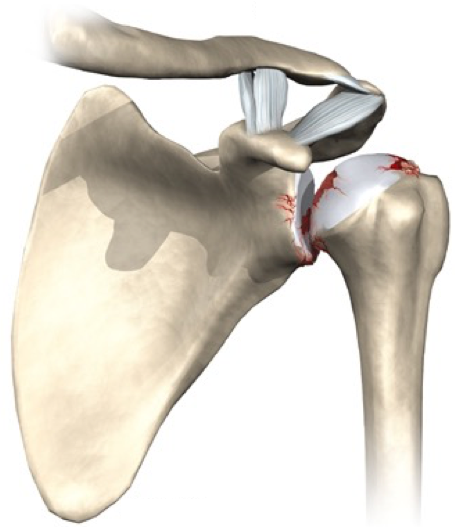

LESÃO DO MANGUITO ROTADOR

O manguito rotador é composto por 4 músculos: supraespinhal, infraespinhal, subescapular e redondo menor. A principal função desse grupo muscular e realizar os movimentos do ombro, bem como a estabilização da articulação. As lesões do manguito rotador constituem a ruptura total ou parcial desses tendões.. As causas da lesão podem ser degenerativas e traumáticas. No paciente idoso, com o processo de degeneração o tendão perde as suas propriedades fibroelásticas e torna-se susceptível ao surgimento dessas lesões. As causas traumáticas são observadas habitualmente em pacientes jovens, mas pode acometer os pacientes mais velhos também. Sintomas como dor no ombro e dificuldade para realizar a elevação do ombro e movimentos rotacionais são as queixas mais frequentes. O tratamento e individualizado para cada paciente. Mas as lesões com ruptura total ou lesões parciais com mais de 50% de extensão, associado a quadro de dor e dificuldade para realizar os movimentos do ombro, tendem a necessitar de cirurgia. Para lesões parciais com menos de 50% com quadro de dor pequeno e um bom movimento do ombro habitualmente indica-se a reabilitação com fisioterapia. A cirurgia utilizado é a artroscopia do ombro, podendo-se realizar a cirurgia aberta em raros casos. Após o procedimento utiliza-se uma tipoia durante cerca de 35 dias, onde após esse período o paciente iniciará a reabilitação fisioterápica.